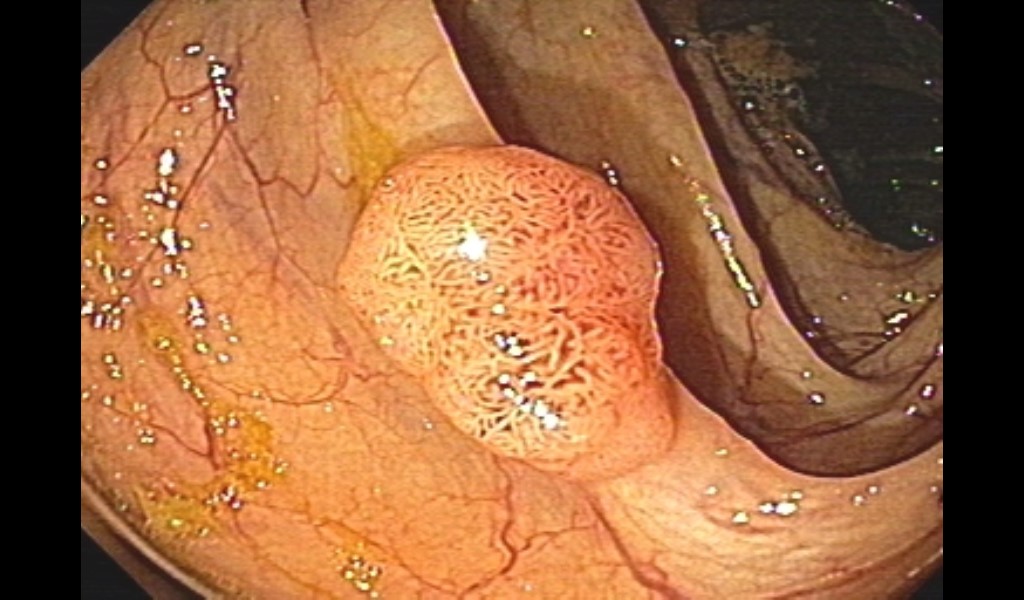

This tool is designed to assist in the detection, segmentation, and classification of colon polyps by processing medical images and providing AI-powered insights.

Colon Polyp Analysis Tool

Uploaded Image

Analysis Results